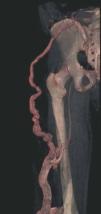

Hoy en día la utilización de los nuevos equipos TC multicorona y RM permiten la adquisición de imágenes con gran rapidez, pudiendo realizar reconstrucciones multiplanares de gran calidad, así como estudios angiográficos no invasivos13,23. Recientemente hemos estudiado 16 pacientes con síndrome de Klippel-Trenaunay mediante una venografía tomografía computarizada multicorte (TCM) o una venografía resonancia magnética tridimensional (RM-3D), utilizando imágenes axiales convencionales, reconstrucciones multiplanares (RMP), proyecciones de máxima intensidad (PMI) e imágenes tridimensionales (figs. 1-3). Las imágenes axiales convencionales fueron de utilidad para evaluar el tejido blando y el hueso y permitieron localizar el sistema venoso profundo y los vasos anómalos superficiales, determinando su relación con estructuras adyacentes. Las imágenes axiales, RMP y PMI fueron empleadas para trazar el origen, trayecto y extensión de las malformaciones venosas. Las imágenes de la superficie cutánea permitieron evaluar la localización y la extensión de la mancha en vino de Oporto y demostrar la hipertrofia de la extremidad. Las reconstrucciones tridimensionales permitieron demostrar las varicosidades y el origen y trayectoria de los vasos aberrantes (figs. 4 y 5). Ninguno de los pacientes requirió otra técnica complementaria invasiva (flebografía convencional) para confirmar el diagnóstico y planificar las estrategia terapéutica24.

Figura 4. Agenesia de la vena poplítea en paciente con síndrome de Klippel-Trenaunay.

Así, podemos concluir que una venografía TC o una venografía RM en 3D en niños y embarazadas para limitar la radiación puede ser la prueba de elección para estudiar a fondo una malformación vascular extensa localizada en una extremidad. Esta técnica permite conocer la localización exacta de la lesión en un plano tridimensional, detectando una posible infiltración musculoesquelética y extensión torácica y/o abdominopélvica, además permite valorar cambios en la densidad ósea (osteoporosis) y dismetrías, así como comprobar la existencia de sistema venoso profundo y su permeabilidad (figs. 6-9). También son de utilidad para detectar anormalidades del sistema venoso superficial, demostrar las presencia de venas aberrantes o ciáticas y determinar su extensión y vía de drenaje. Aunque estos procedimientos siguen siendo inferiores a la arteriografía o flebografía convencionales al no proporcionar el mismo grado de información sobre la hemodinámica de la malformación, representan un avance muy significativo, y en nuestra experiencia sólo será necesaria la complementación con procedimientos invasivos en casos de hipoplasias vasculares donde no esté claro el funcionamiento hemodinámico del vaso24,25.